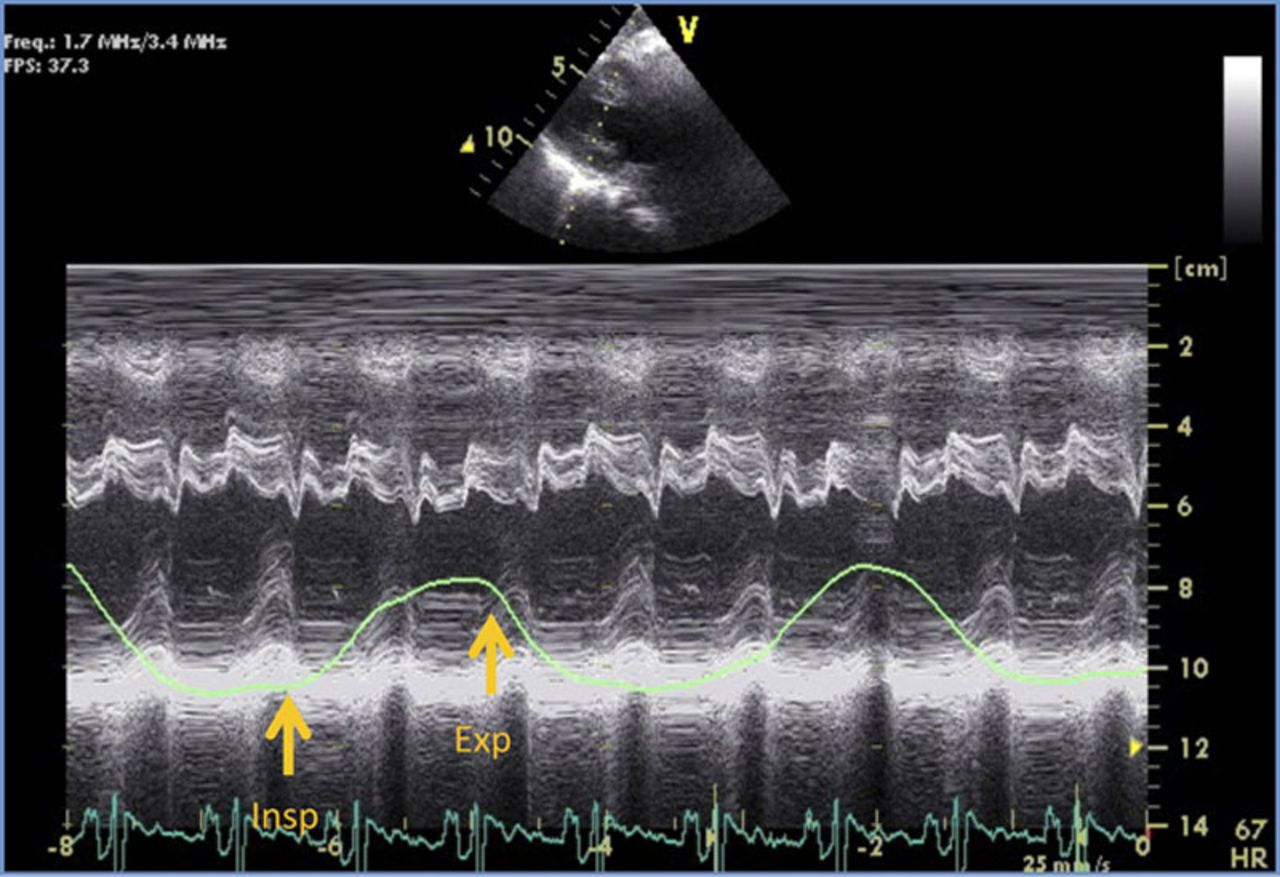

The M-Mode demonstrates and is an example of what cardiac pathology?

Constrictive Pericarditis

The M-Mode findings for constrictive pericarditis include all the following, EXCEPT:

Flat inferior-lateral wall in diastole

Paradoxical septal motion/notching of the septum

Left atrial enlargement

Bright dense pericardium

Left ventricular enlargement